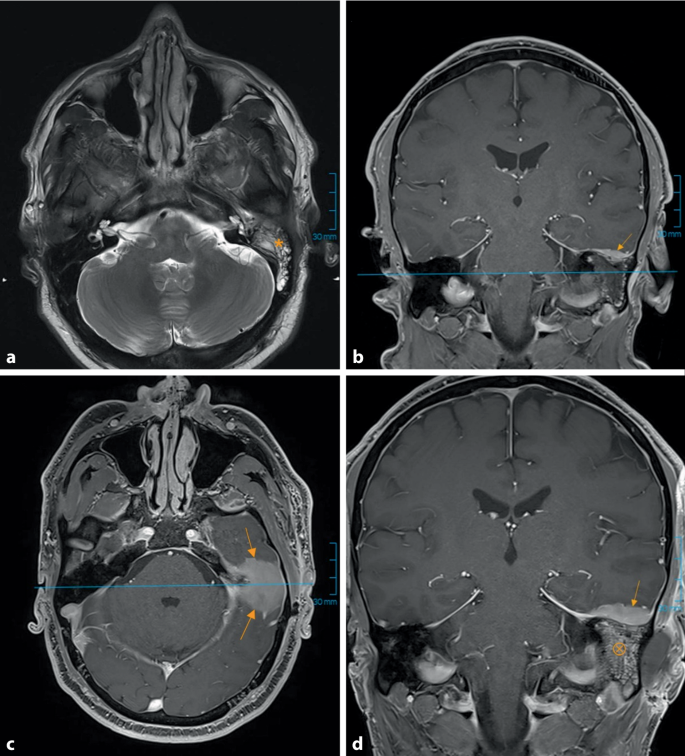

首次乳突切除术(a)和再次乳突切除术(c、d)前的头部MRI图像。初始T2序列(a)显示乳突腔内积液,边缘可见对比剂吸收;T1-VIBE序列(b)显示左侧乳突骨质增厚(箭头),考虑为局部脑膜炎。后续图像(d)显示乳突腔内软组织肿胀,骨膜层模糊,提示可能为脑膜炎症。

为处理乳突病变进行了乳突切除术。术中取样的组织主要为坏死组织,病理检查无显著发现。MRI随访显示颞叶开始出现水肿。怀疑亚急性乳突炎伴脑膜受累,给予哌拉西林/他唑巴坦抗生素治疗。出院时建议患者持续使用抗菌滴耳液。后续复查时肿胀持续加重,再次取样检查。在获得病理结果前,患者因疼痛加剧再次住院。实验室检查和血液培养未见异常。根据MRI提示可能存在脑脓肿,按诊疗指南给予美罗培南/万古霉素静脉注射治疗。随后进行再次乳突切除术以获取更多组织样本。术中发现乳突内有肿瘤样组织并向颞侧扩散(图2)。最终病理检查确诊为髓系肉瘤,为先前缓解的AML的髓外复发。